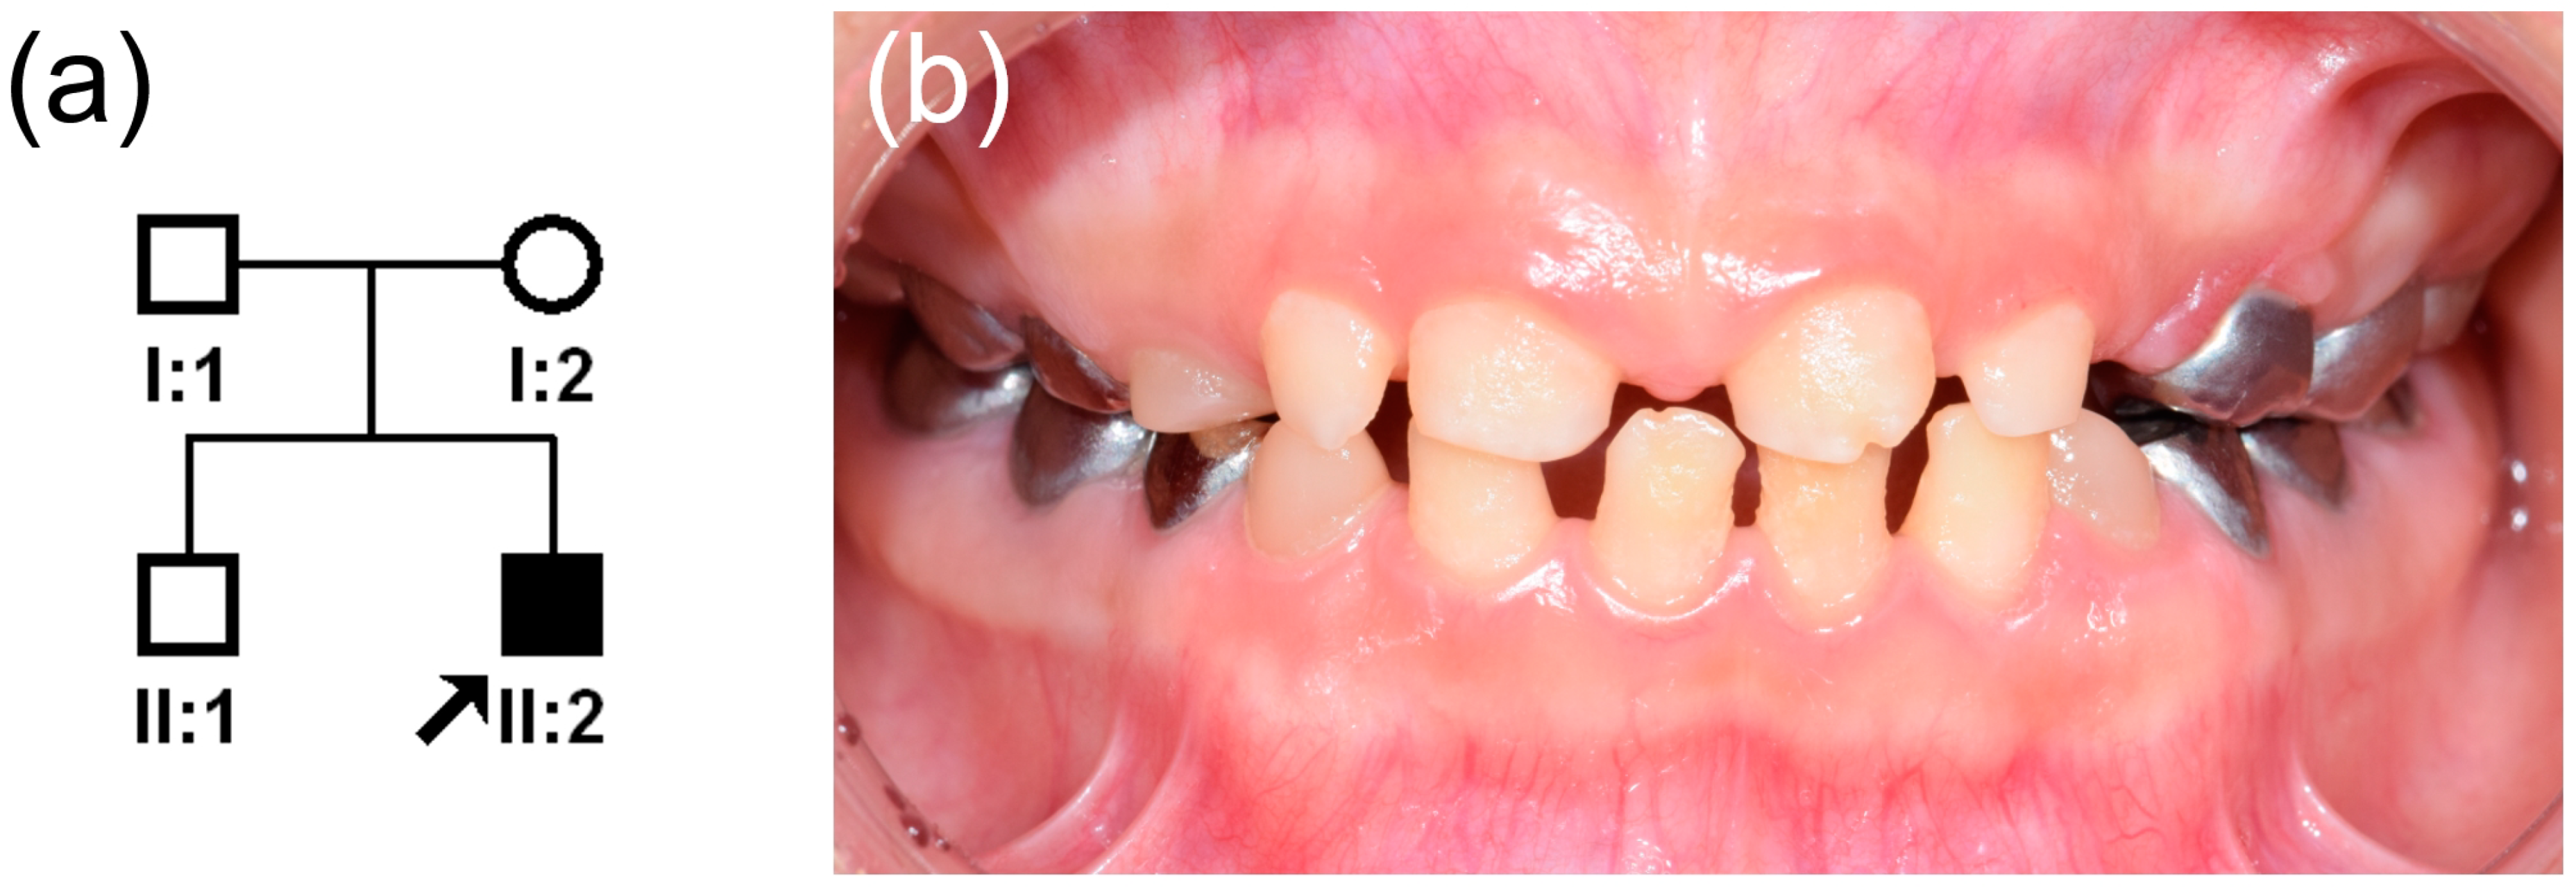

A Novel De Novo SP6 Mutation Causes Severe Hypoplastic Amelogenesis Imperfecta